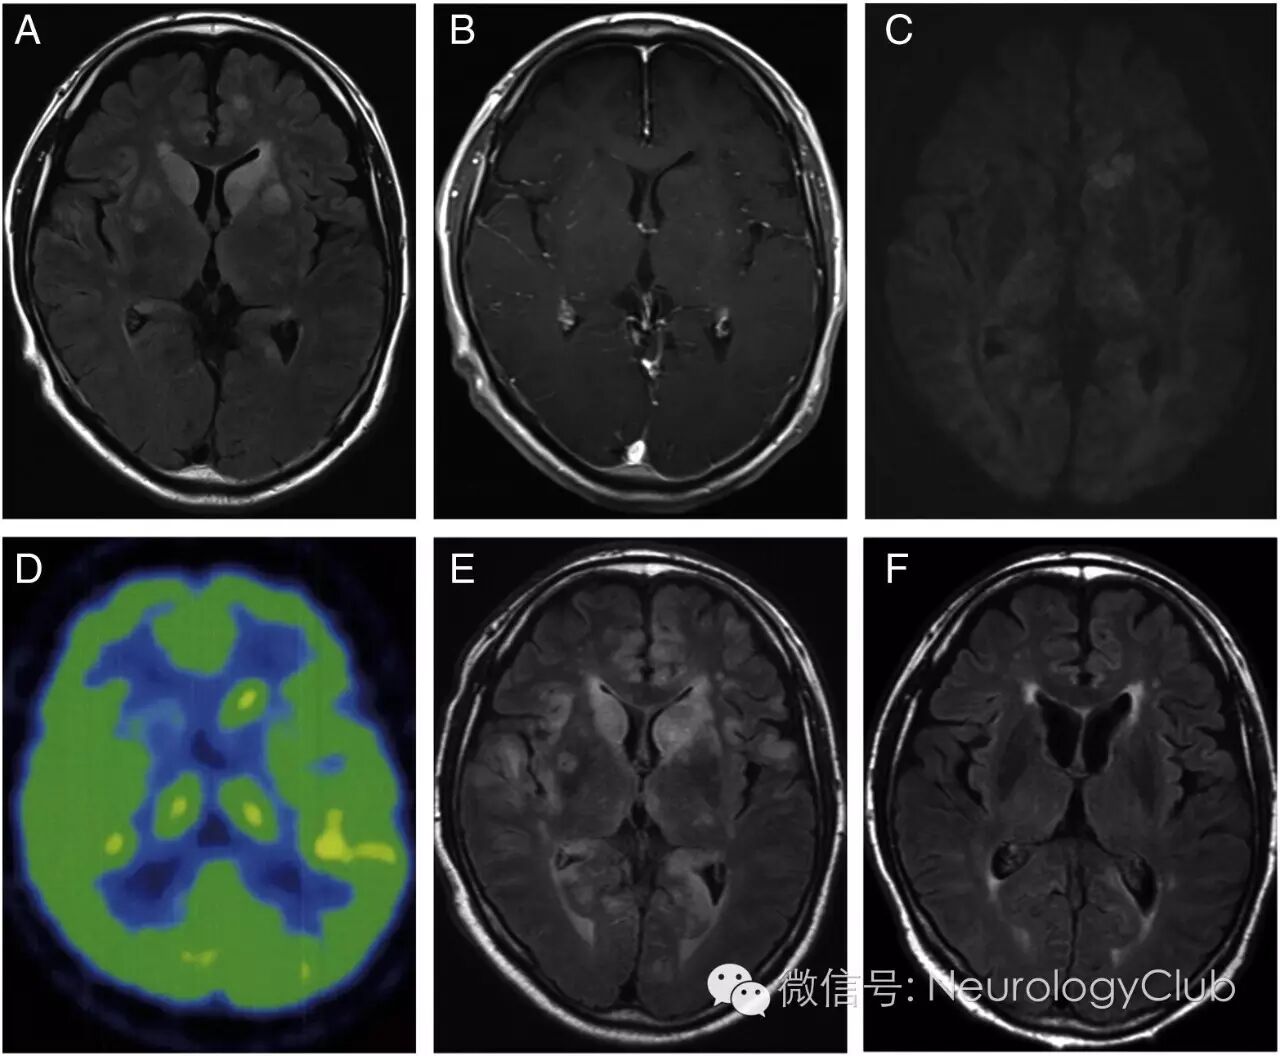

67岁男性,表现为行走不稳,地形定向障碍和尿失禁。患者出现嗜睡被送至医院。体温38°C,体格检查未见浅表淋巴结肿大或肝脾肿大,呈嗜睡状态。神经系统查体无颈项强直或Kernig征。下肢肌力变差,上肢有轻度强直。颅神经,感觉功能,协调功能和自主神经功能正常。实验室检查无白细胞增多,但38%为异常淋巴细胞,C反应蛋白升高(2.43mg/dl)。血清可溶性白细胞介素-2受体(sIL-2R)浓度很高(53416 U/ml)。脑脊液检查提示细胞数增多(110/mm3单核细胞和2/mm3多核细胞),可见花瓣样细胞(flower cells),蛋白140.6mg/dl,sIL-2R浓度29810U/ml,糖57mg/dl(血糖131mg/dl)。患者血清和脑脊液抗HTLV-I抗体阳性。磁共振T2WI可见双侧尾状核对称性高信号病灶(图1A),注射对比剂后未见强化(图1B)。DWI可见左侧尾状核高信号病灶(图1C)。PET证实氟代脱氧葡萄糖(FDG)摄取增多,标准摄取值7.8(图1D)。患者病情逐渐恶化,陷入昏迷。入院4周后复查磁共振可见双侧顶叶皮层高信号新病灶,双侧尾状核的病灶仍然存在(图1E)。

(图1:A:T2WI可见双侧尾状核对称性高信号病灶;B:T1增强病灶无明显强化;C:DWI上可见左侧尾状核高信号病灶;D:氟代脱氧葡萄糖(FDG)PET证实双侧尾状核代谢增高,标准摄取值7.8;E:入院4周复查磁共振T2WI可见除双侧尾状核外,双侧顶叶皮层高信号病灶;F:化疗后病灶部分缓解

患者转至血液科病房,化疗后意识状态仅短暂缓解。再次复查磁共振病灶部分好转(图1F)。但是,起病6月后患者因呼吸衰竭去世。患者家属拒绝尸检 。